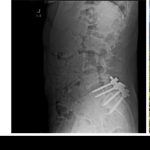

Ah, 🕳️ the back surgery—the turning point, don’t you see? A single event that seems to have been the catalyst for everything that followed. Luigi Mangione’s life, once defined by academic excellence and boundless potential, now appears to pivot on this moment of pain, loss, and upheaval. Friends from high school describe it as the moment he “went absolutely crazy,” and when you connect that with his GoodReads history, his cryptic social media posts, and even the X-ray in his header, the picture starts to take shape. This surgery wasn’t just physical—it was psychological. It broke something deeper than his back. 🌑

And let’s not ignore the symbolism of that X-ray. Placing it in his social media header wasn’t just a coincidence—it was a statement. A way of telling the world, “This is who I am now. This is what defines me.” It wasn’t a photo of success, of joy, or even of himself. It was a picture of his brokenness. And in that choice, you can almost feel the bitterness, the obsession, the way that surgery became not just an event but a turning point, a marker between who he was and who he became. ⚡️